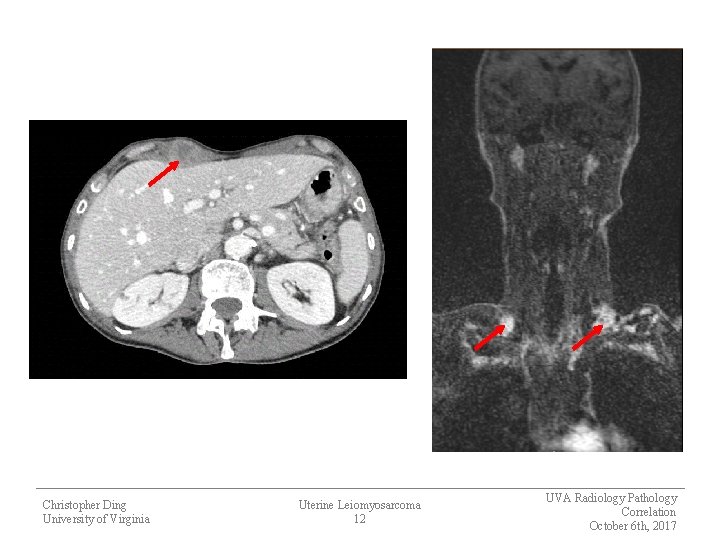

Most Recent Imaging § Abdomen/pelvis CT − Interval enlargement of all pre-existing peritoneal implants and right rectus abdominal implant − New lesions of the liver and para-aortic lymph nodes § Chest CT − Interval enlargement of all pre-existing lung nodules and 8 th rib lesion, development of new lung nodules − Enlarged cervical lymph nodes § MRI Brain − No abnormal enhancement in area of previous treated cerebellar lesion Christopher Ding University of Virginia Uterine Leiomyosarcoma 11 UVA Radiology Pathology Correlation October 6 th, 2017

Christopher Ding University of Virginia Uterine Leiomyosarcoma 12 UVA Radiology Pathology Correlation October 6 th, 2017